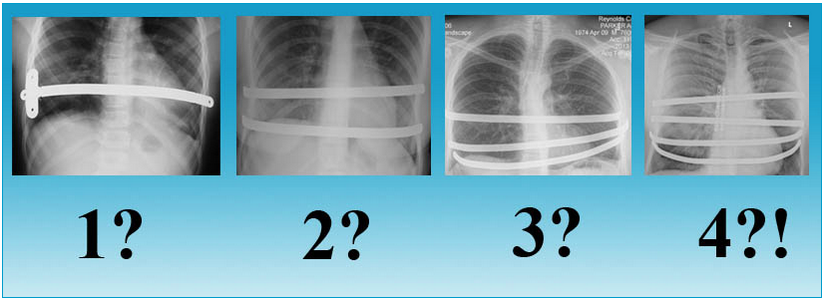

- Рентгеновские снимки грудной клетки до и после процедуры; “S” означает положение воронкообразного углубления до и после операции.